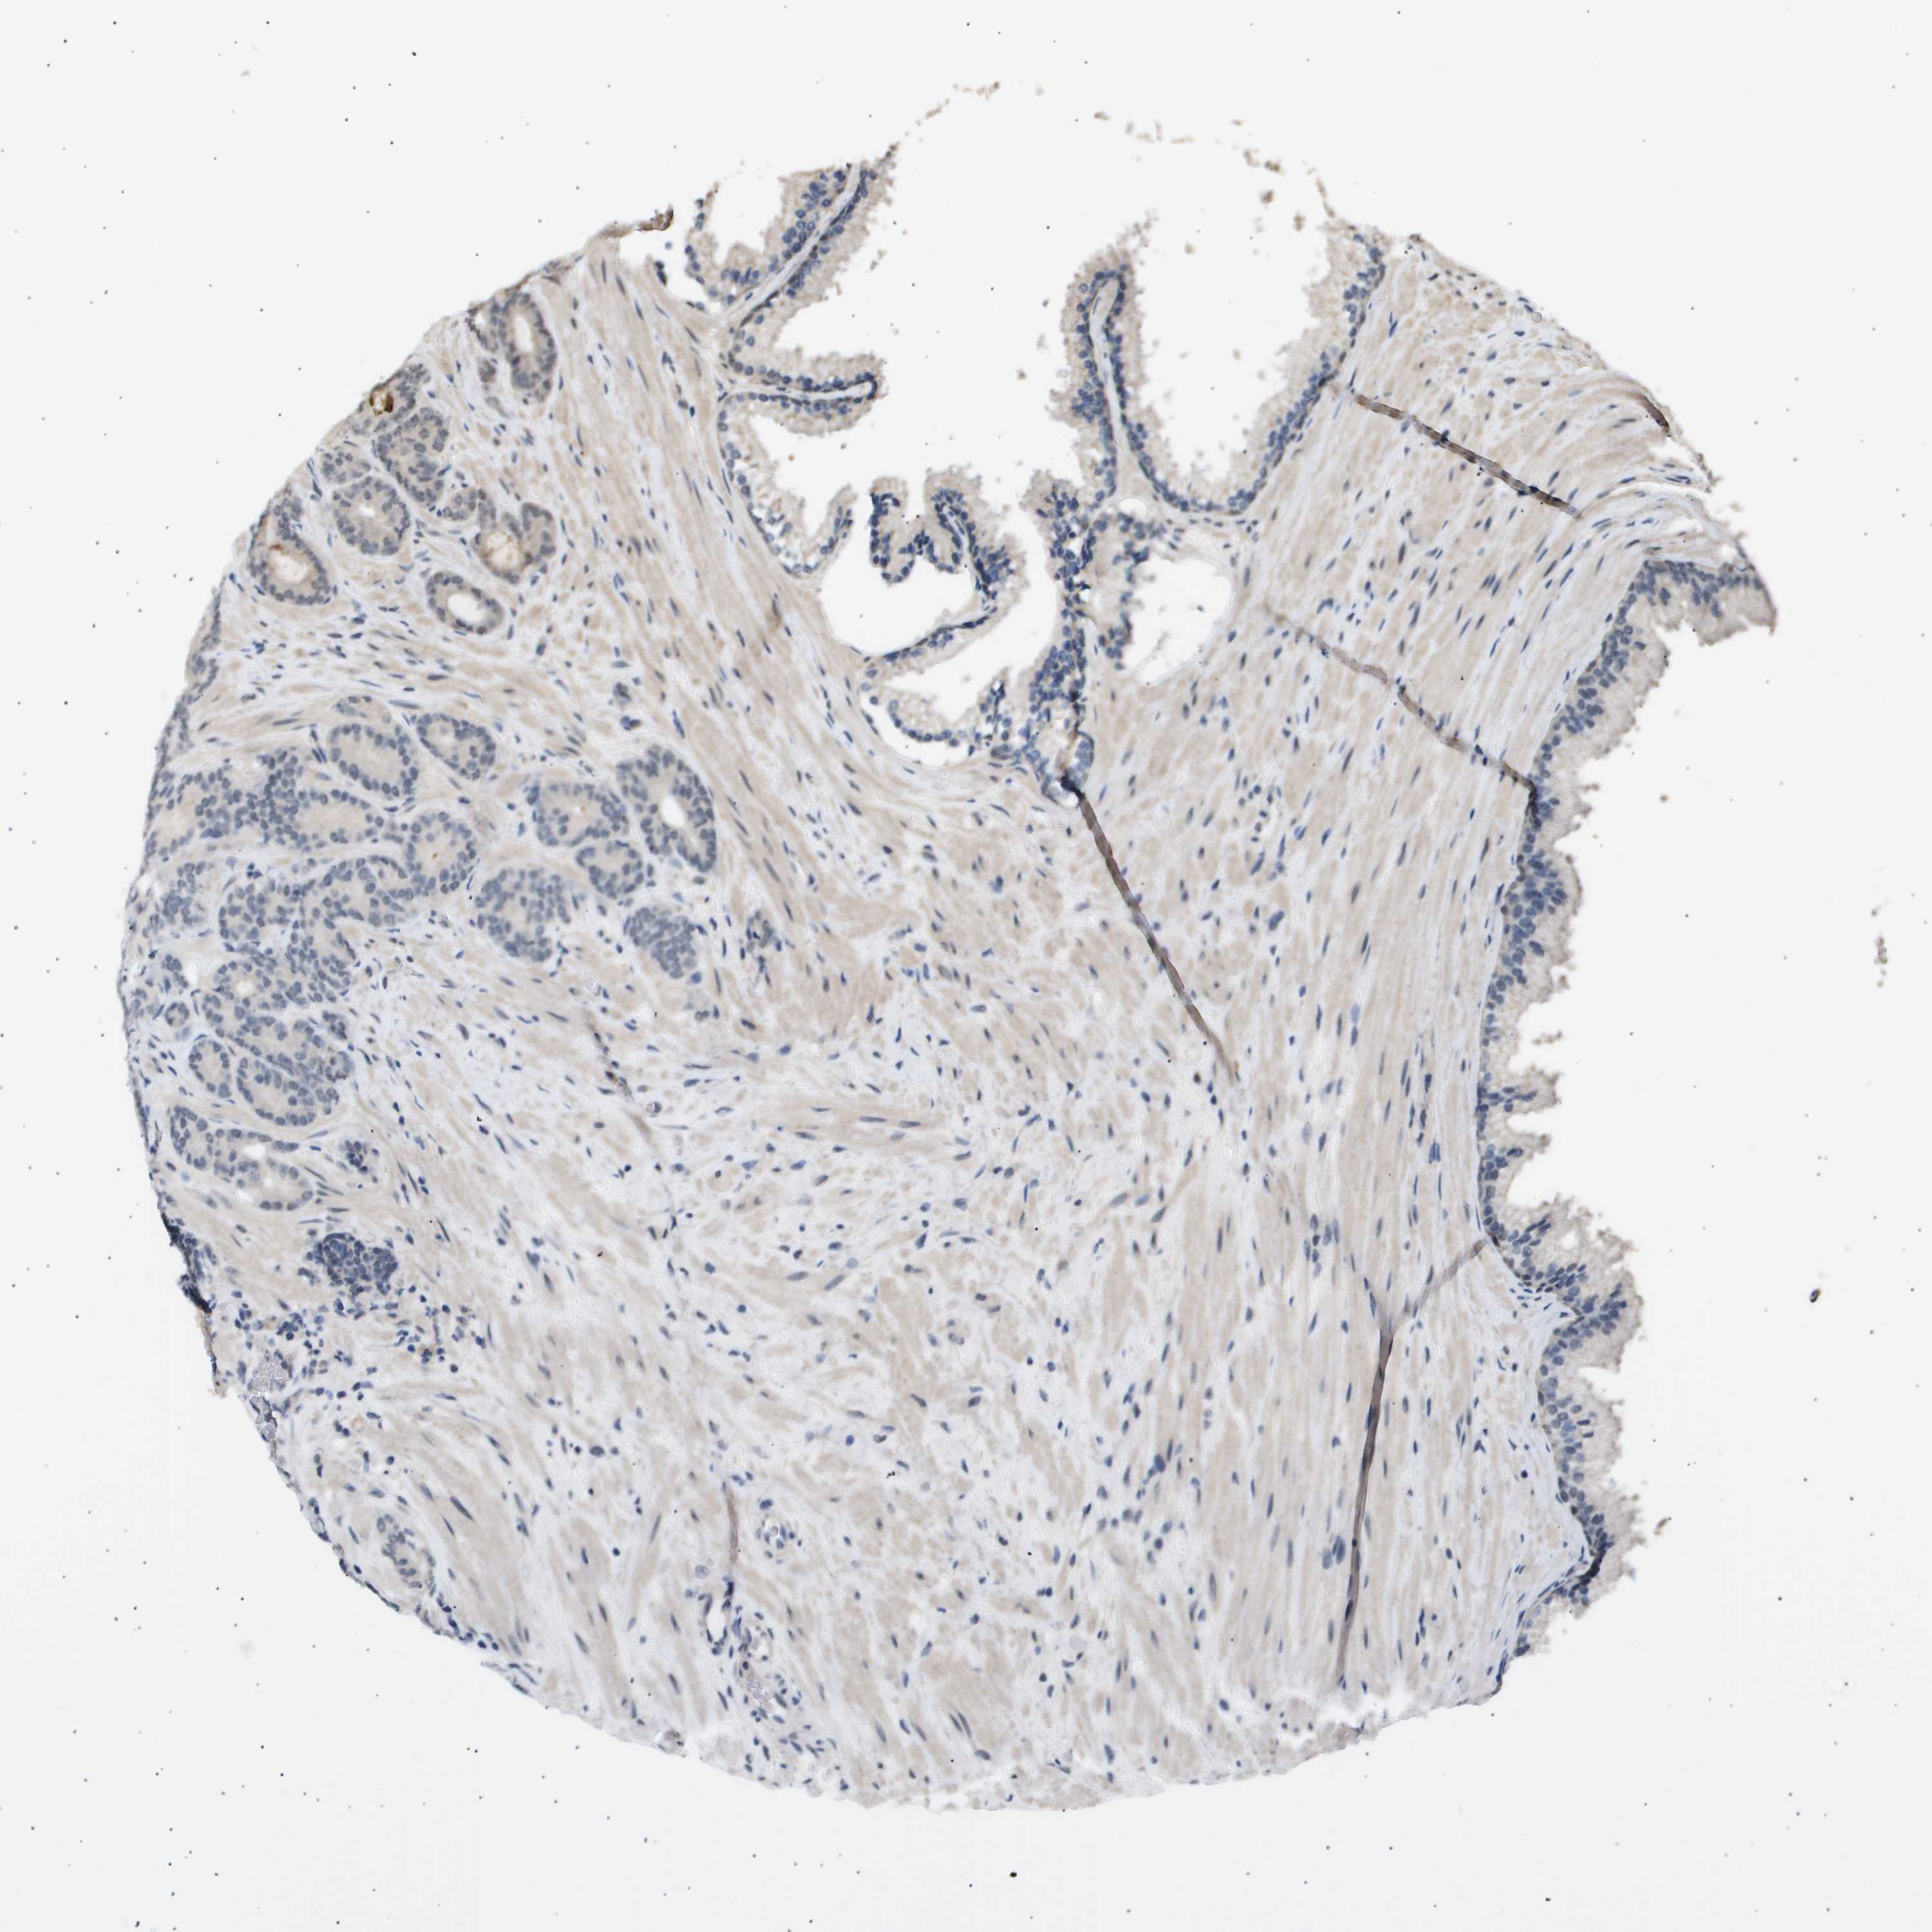

PROSTATE CANCER - Protein expressioni

A mouse-over function shows sample information and annotation data. Click on an image to view it in a full screen mode. Samples can be filtered based on level of antibody staining by selecting one or several of the following categories: high, medium, low and not detected. The assay and annotation is described here.

Antibody stainingi

Antibody staining in the annotated cell types in the current human tissue is reported as not detected, low, medium, or high, based on conventional immunohistochemistry profiling in selected tissues. This score is based on the combination of the staining intensity and fraction of stained cells.

Each image is clickable and will lead to virtual microscopy that enables deeper exploration of all samples and also displays staining intensity scores, fraction scores and subcellular localization as well as patient and tissue information for each sample.

Antibody CAB016136

Antibody CAB017773

Staining

High

Medium

Low

Not detected

Intensity

Strong

Moderate

Weak

Negative

Quantity

>75%

75%-25%

<25%

None

Location

Nuclear

Cytoplasmic/membranous

Cytoplasmic/membranous,nuclear

Adenocarcinoma, Low grade

Adenocarcinoma, High grade